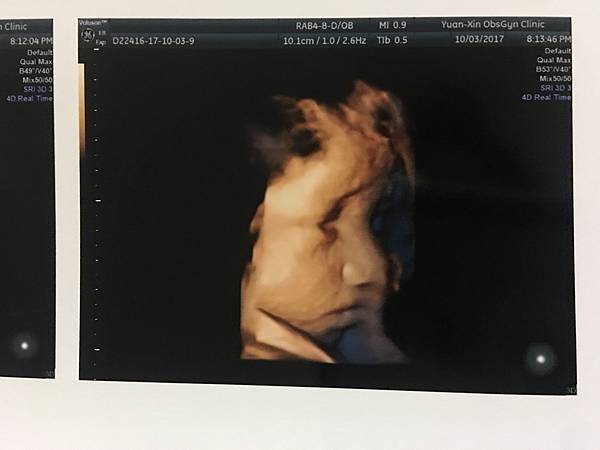

【卸貨倒數29天】10/3 第33週產檢